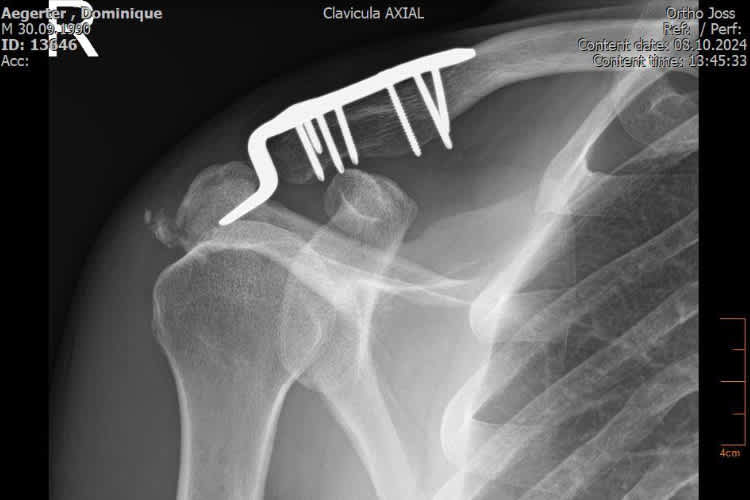

Am Dienstagnachmittag ließ Dominique Aegerter zu Hause in der Schweiz mittels einer Computertomographie neues Bildmaterial anfertigen, um seinen Heilungsfortschritt zu dokumentieren. Der 34-Jährige hat sich bei einem Trainingsunfall mit dem Mountainbike am 28. August auf der rechten Seite vier Rippen gebrochen, dazu das Schlüsselbein; das Schulterblatt und Schulterdach waren angebrochen.

Domi verpasste die Rennen in Magny-Cours, Cremona und Aragon, am kommenden Wochenende will er in Estoril wieder angreifen. Es dauerte bis Donnerstagabend, bis die Dorna mitteilte, dass der zweifache Supersport-Weltmeister am Freitagvormittag am FP1 teilnehmen darf; danach muss er erneut bei Monica Lazzarotti vorstellig werden, der verantwortlichen Ärztin für die Superbike-WM. Die sehr gewissenhafte Italienerin hat Bedenken wegen einer Rippe. "Die Knochen waren nach dem Bruch etwas verschoben und wurden abgeschliffen, weil sich die Rippe nicht operativ befestigen ließ", erklärte Aegerter im persönlichen Gespräch mit SPEEDWEEK.com. "Die Rippe ist noch nicht 100-prozentig zusammengewachsen und in der Nähe der Lunge. Falls ich wieder drauffalle, wäre das gefährlich für meine Gesundheit." "Am Montag schaffte ich eine Liegestütz, heute hat sie mir nach sechs gesagt, dass ich aufhören darf", schmunzelte der Yamaha-Pilot. "Ich habe mehr Angst, dass meine Schulter nicht genügend Kraft hat, um Höchstleistungen zu zeigen, als wegen der Rippe. Klar habe ich mit ihr das Risiko, wenn ich drauffalle. Wenn ich normal wegrutsche, dann macht das nichts. Wenn ich einen Highsider habe, dann kann alles mögliche kaputt sein, wenn es blöd hergeht."